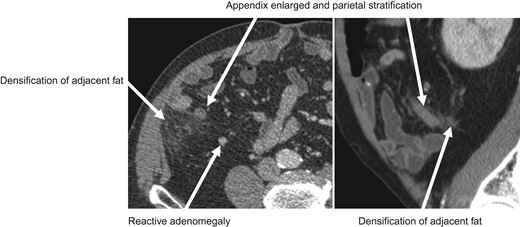

At physical examination, the patient was distressed, with body temperature of 37°C, hemodynamically stable, no signs of respiratory distress. The abdominal examination revealed the presence of positive Rovsing and Blumberg signs and no palpable masses. Laboratory tests were performed, yielding the following results: white blood cell count, 10.3 × 10^3cells/μL; neutrophil proportion, 77.2%; hemoglobin level, 14.4 g/dl; platelet count 149 × 10^3cells/μl; C-reactive protein 32.77 mg/l; sodium 141 mmol/l; creatinine 1.06 mg/dl. Without changes in the coagulation study. Abdominal ultrasound (Fig. 1) and CT scan (Fig. 2) revealed the findings consistent with appendicitis.